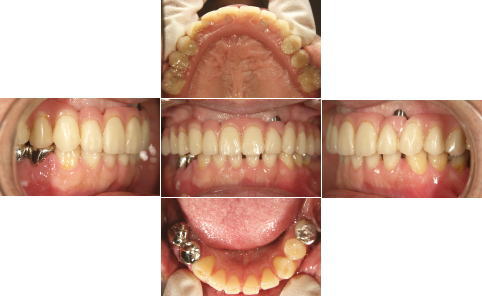

| 治療前 | 治療後 |

| 関西から通っている患者様です。 近々お嬢様の結婚式があるため、その前に上下共、All-on-4で治療して欲しいと来院されました。 右下親知らずは埋伏歯なので残してあります。 |